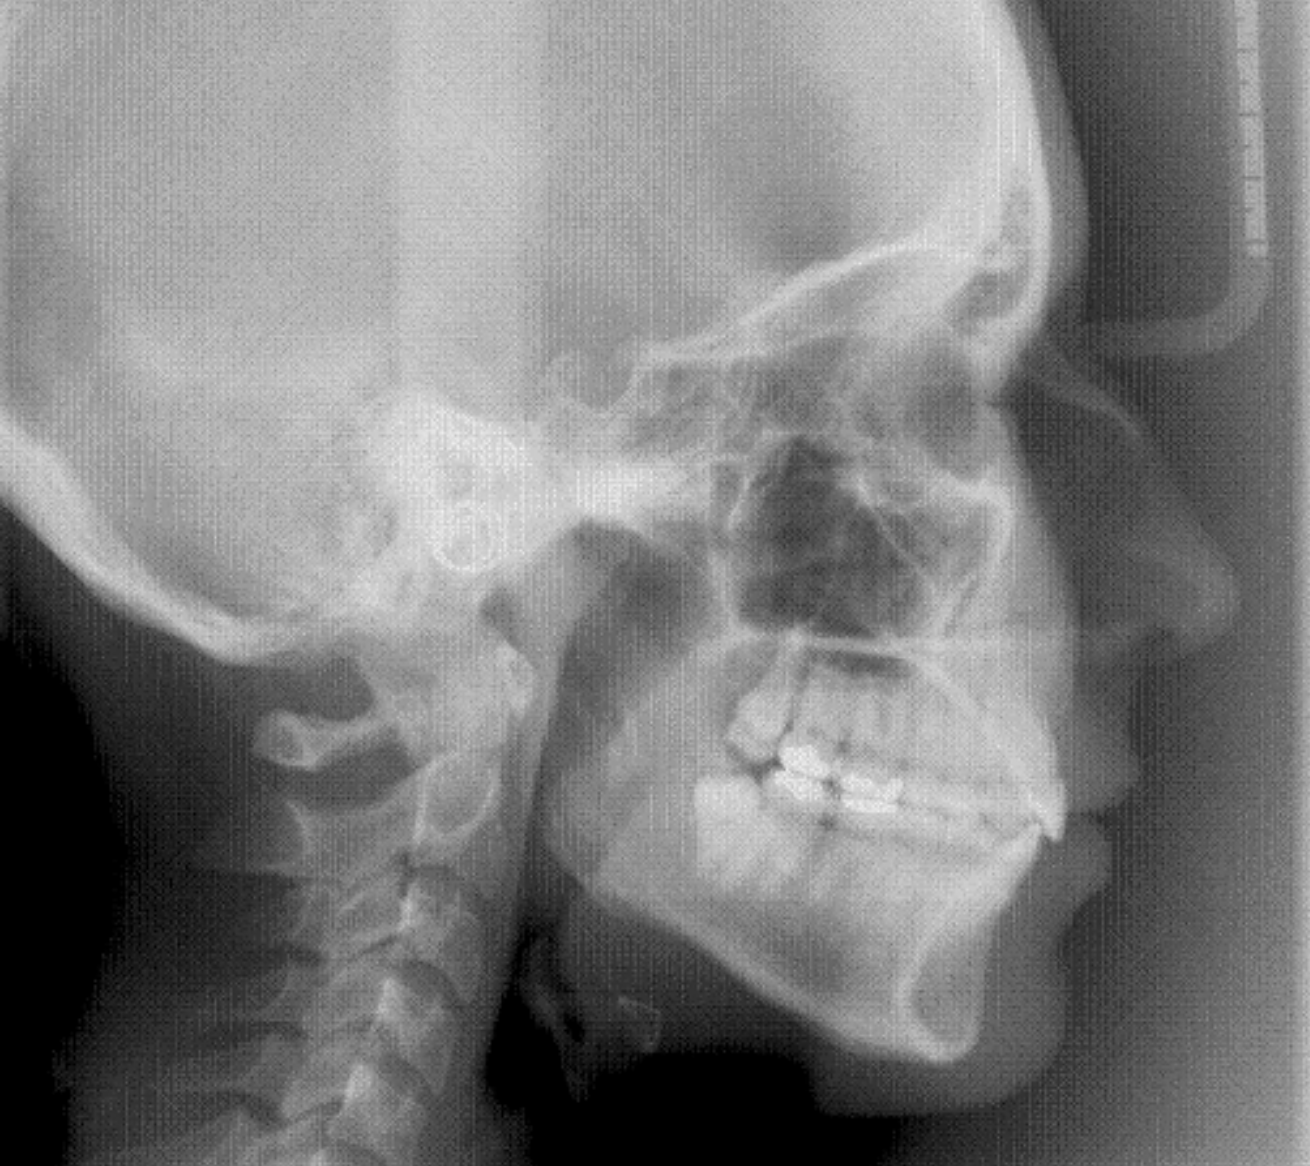

La Teleradiografía lateral de cráneo permite efectuar una valoración cefalométrica , de interés en ortodoncia y cirugía ortognática